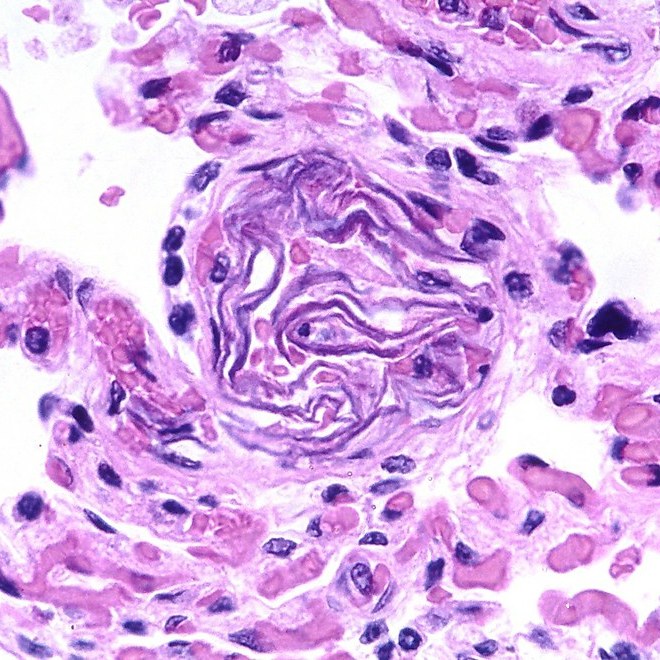

- “Amniotic fluid embolism” by Pulmonary Pathology is licensed under CC BY-SA 2.0